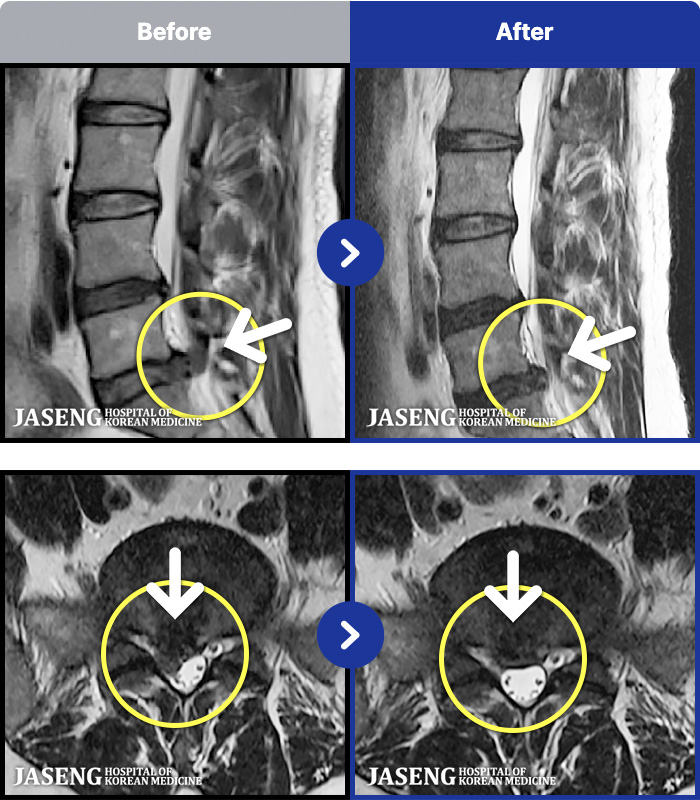

MRI ũ ʸ Ȯϼ.